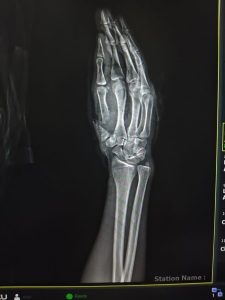

ومن جانبه أوضح الدكتور مجدي القاضي عميد كلية الطب البشري ورئيس مجلس إدارة المستشفيات الجامعية، أن الفريق الطبي نجح في إعادة زرع إصبع الإبهام باستخدام جراحة ميكروسكوبية دقيقة استغرقت نحو 6 ساعات، تم خلالها توصيل الشرايين والأوردة والأعصاب المغذية للإصبع، بالإضافة إلى تثبيت عظام الإصبع باستخدام أسلاك معدنية، مما ساهم في استعادة الدورة الدموية واستقرار الحالة.